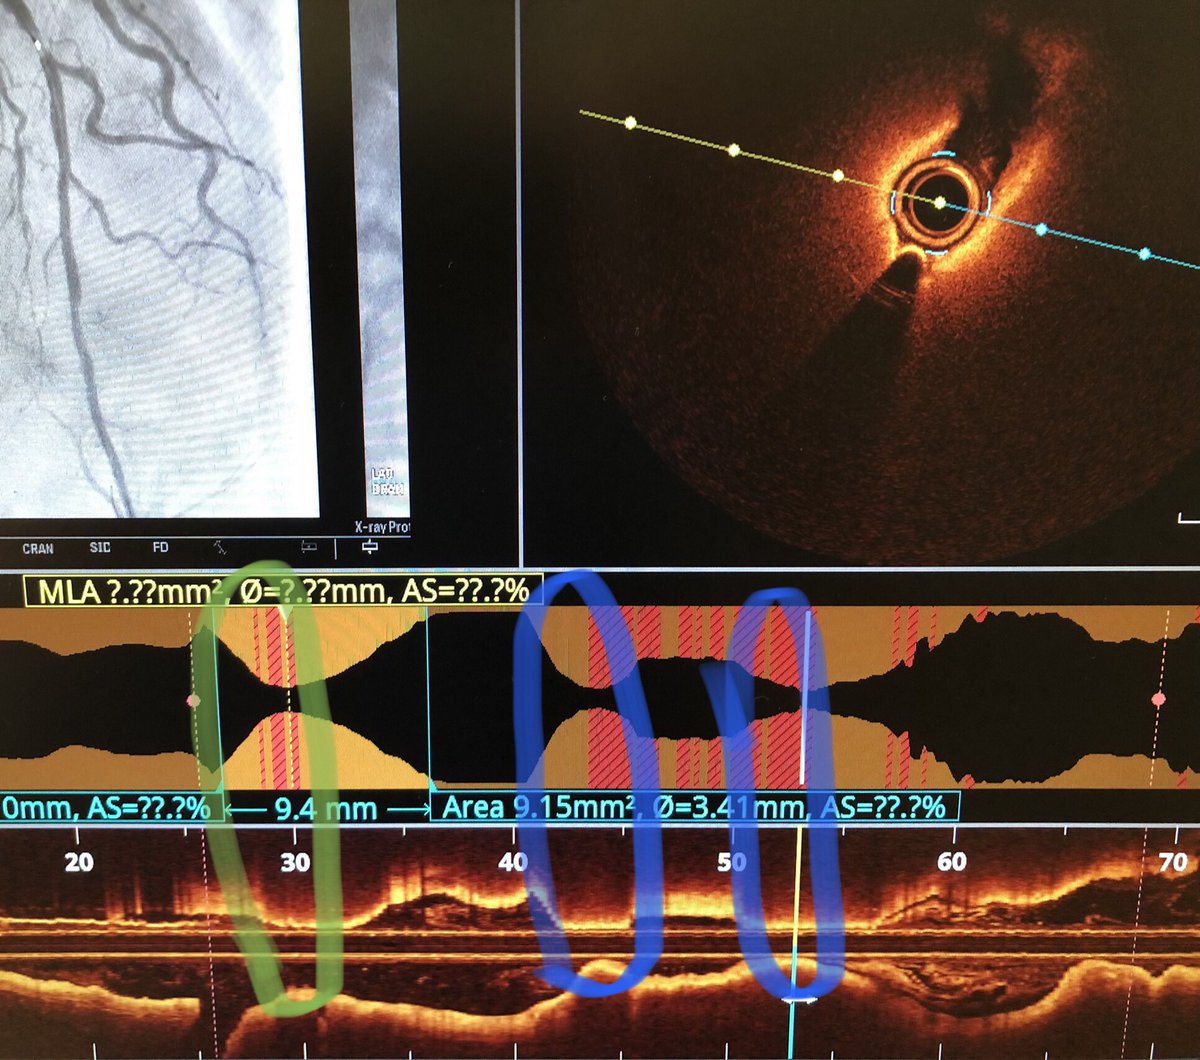

OCT conundrum 🤔 OCT run of this mid-LAD lesion (Fig 1) confirms tight stenosis (circled green) But where did these other two surprise lesions (circled blue) come from ???? #RadialFirst